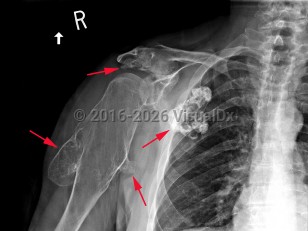

Multiple hereditary exostoses

A rare, autosomal dominant genetic condition resulting in the development of multiple osteochondromas (exostoses) at the metaphyses or diaphyses of long bones, commonly affecting the vertebrae, ribs, limbs, hands, fingers, shoulders, and hips. Caused by mutations in the EXT1 or EXT2 genes. Osteochondromas are benign tumors consisting of bone overgrowths and capped with cartilage. They begin formation during regular bone growth and stop growing when the patient reaches skeletal maturity. The severity of the condition is widely variable. The presence of osteochondromas can cause pain, short stature, various deformities, limb length discrepancy, hip dysplasia, and movement difficulties. The deformities may also cause nerve, blood vessel, or spinal cord compression. Most exostoses remain benign, but some may become malignant.